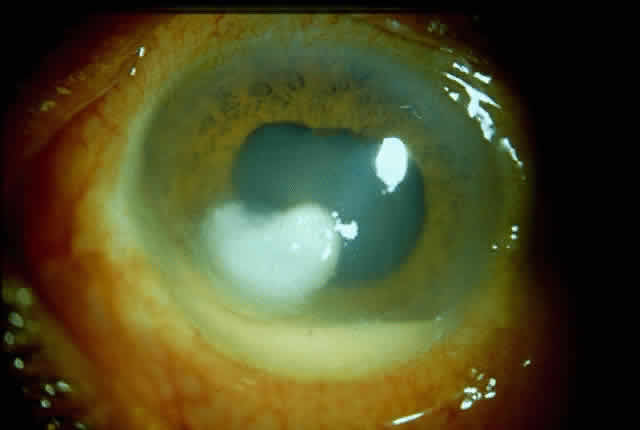

Bacterial corneal infections are caused by a wide variety of organisms. Pneumococcus seems to be the most common causative organism (Fig. 2); however, staphylococcal, pseudomonal, and gonococcal infections frequently are encountered.3 This may be related to chronic dacryocystitis.5

Fig. 2. Photograph demonstrating a pneumococcal corneal ulcer.